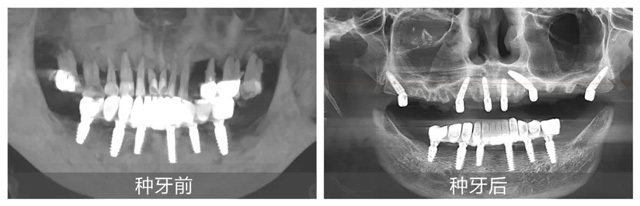

在配備數(shù)字化導(dǎo)板系統(tǒng)的現(xiàn)代化手術(shù)室里,黃杰終于迎來(lái)期盼已久的“試煉場(chǎng)”。短短一年,就已經(jīng)成功種植修復(fù)2100+顆牙,完成無(wú)牙頜即刻負(fù)重手術(shù)110臺(tái)。不僅在種牙數(shù)量上取得了突破,在質(zhì)量方面也同樣出色。

日前,黃杰為一位種牙顧客實(shí)施“即拔即種”手術(shù),從拔除殘根到植入種植體僅用15分鐘,創(chuàng)面控制得如同經(jīng)過(guò)精密計(jì)算一般。但讓他最有成就感的,還是那些從牙槽外科延續(xù)而來(lái)的“全流程治療”:曾有位患者因埋伏多生牙導(dǎo)致囊腫,他先微創(chuàng)拔除患牙,待運(yùn)用頜面外科的骨移植修復(fù)骨缺損后又為其完成種植修復(fù)。“能看到顧客從治療到重獲咀嚼功能的完整過(guò)程,這是口腔醫(yī)生特有的幸福。”